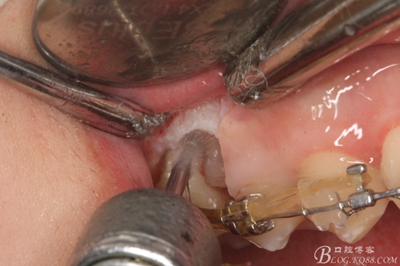

圖8.因16與14合面的間隙僅2mm左右,牙根無法合向脫位,如何考慮15牙根的脫位將是最大問題。高速手機去除牙間隙內(nèi)的覆蓋在15牙根表面的牙齦組織

圖10.去除牙齦組織后。露出15牙根斷面,合面無法脫位